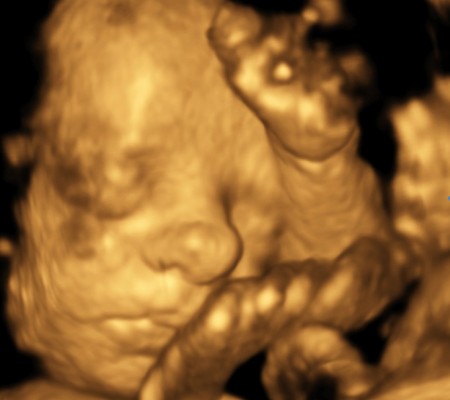

3D i 4D tehnologija omogućava da vidimo površinu bebe na lepši način i pokrete ploda u realnom vremenu.

Takođe nam omogućava da bolje vidimo fetalne mane na licu, šakama i stopalima.

Kao i 2D, 3D i 4D koriste ultrazvučni talas da se kreira slika bebe u materici. 3D je kreirana slika u prostoru dok 4D prikazuje pokret unutar materice pa možemo videti kako se beba smeje, mršti ili zeva.

Za prikaz ovih preseka potrebni su odgovarajući uslovi kao što su položaj ploda (lice ka nama), normalna količina plodove vode, poželjno je da ruke, noge i pupčanik ne budu ispred bebinog lica. U neodgovarajućim uslovima ovaj snimak nije moguće napraviti.

Da bi se dobile dobre slike poželjno je da se pregled radi između 24 i 32 nedelje trudnoće.